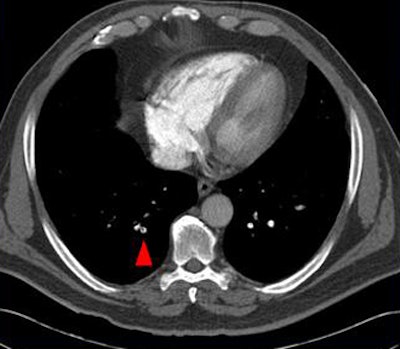

| Above, small peripheral pulmonary emboli are common and are of unknown clinical importance. Image below shows a patient with classic pulmonary embolism, with larger clots involving the central pulmonary vasculature and deep vein thrombosis. All images courtesy of Jane Suh and Dr. John Cronan. |